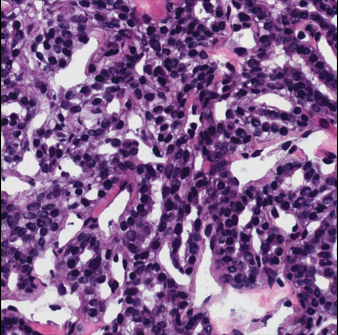

Refer to caption

(a)

(b)

Figure 1: Example of nuclei segmentation. Sample histopathology image and its pixel-level annotations.

The effectiveness of MultiResUNet is largely due to the MRBs, which can capture information at multiple scales by combining features from various pathways. As shown in Fig. 1, the size and proximity of foreground regions can vary greatly, making it important to integrate multi-scale features that can encompass both local and global contexts. By interacting at different resolutions, this model can capture intricate details and contextual nuances necessary for precise segmentation.